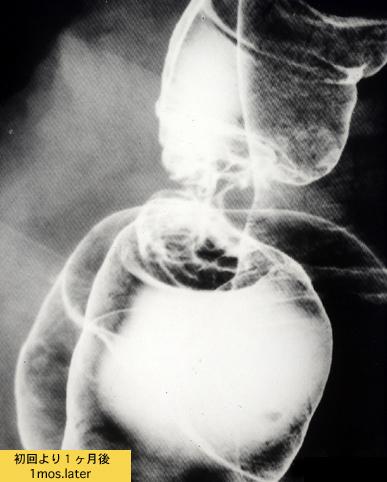

A case of colonic stenosis mimicking an advanced cancer in which pancreatitis involved the left colon(1980's).

[ Image ID:6772 ]

Tumor-like lesions/Invasion from neighbouring organ or tissue

Large intestine(Colon)/Descending colon

X-ray

35 - 40